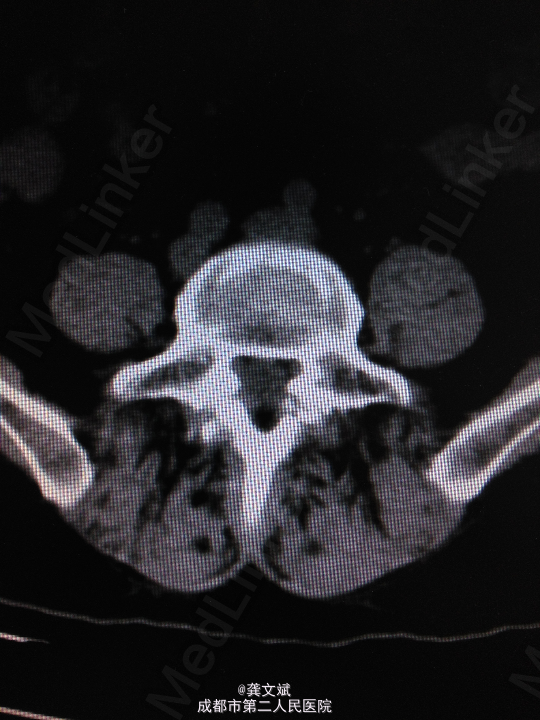

患者女,67岁,因“腰腿痛2月”入院。患者于入院前2月,无明显诱因出现腰腿痛,弯腰时腰痛加剧,无下肢麻木症状及乏力,无大小便障碍。于当地医院行X线提示要5滑脱。

腰5椎体棘突台阶感,腰5水平棘突、椎旁压痛、叩击痛。双下肢肌力、肌张力正常,双侧直腿抬高试验(+)。

诊断:腰5椎体滑脱(I°)、腰5椎体双侧峡部裂 处理:腰5椎间盘摘除、滑脱复位、椎间植骨融合内固定